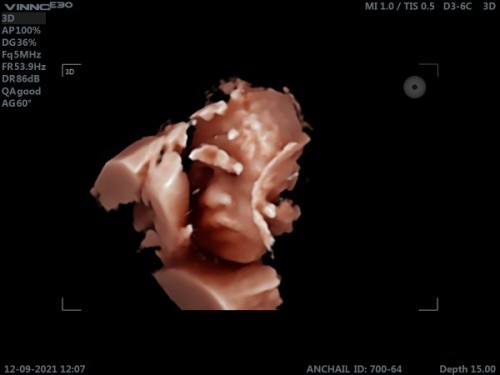

โชว์รูปอัลตร้าซาว4D

มีลูกสาวบ้านไหนโชว์ขนาดนี้ไหมคะแม่ๆ55555เอ็นดูนางทำ😁😍❤